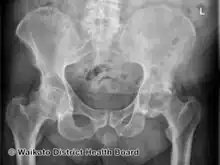

In psoriatic arthritis, pain can occur in the area of the sacrum (the lower back, above the tailbone),[3] as a result of sacroiliitis or spondylitis, which is present in 40% of cases. Pain can occur in and around the feet and ankles, especially enthesitis in the Achilles tendon (inflammation of the Achilles tendon where it inserts into the bone) or plantar fasciitis in the sole of the foot.[3]

• Spondyloarthritis (M07.2): This type is characterized by stiffness of the neck or the sacroiliac joint of the spine, but can also affect the hands and feet, in a similar fashion to symmetric arthritis.